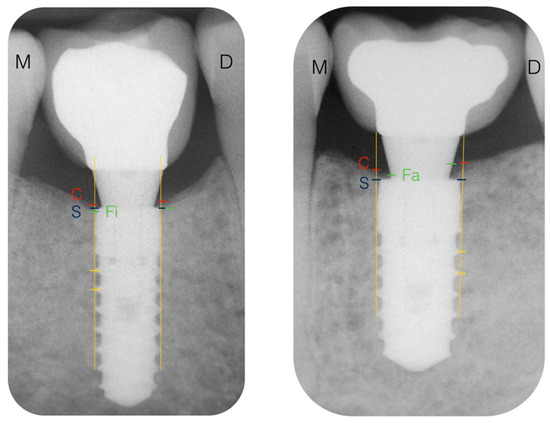

3.6. Radiographic Variables: Changes of Marginal Bone Level (CMBL)

- Marginal bone level at the crest (MBLc): There were no statistically significant differences between groups (p = 0.12). Analyzing the MBLc according to the moment when it was measured, there were statistically significant differences between all surgeries and the rest of the moments of registration (4, 8, and 12 weeks and 6 and 12 months). There were no statistically significant differences (p = 0.00) between the MBLc at all follow-up visits.

- Marginal bone level at the implant (MBLi): There were no statistically significant differences between groups (p = 0.195). Analyzing the MBLi according to the moment when it was measured, there were statistically significant differences only between the moment of surgery and 12 weeks. There were no statistically significant differences (p = 0.00) between the MBLi at any other moment.

- Marginal bone level at the abutment (MBLa): There were statistically significant differences between groups (p = 0.042). Analyzing the MBLa according to the moment when it was measured, there were statistically significant differences (p = 0.024) between the moment of surgery and all of the follow-up visits. Bone contact at the abutment was observed in 51.35% and 61.7% of the implants at 4 and 12 weeks, respectively. These values remained constant after 6 and 12 months with a rate of 63.6% and 67.6%. At the end of the observation period (one year), 66.6% of the implants in Group A and 68.75% in Group B showed bone contact at the abutment. None of these differences were statistically significant.